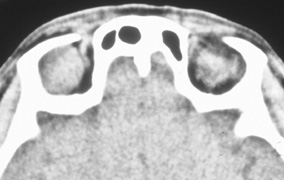

Valuable information about the nature and extent of an orbital pathologic process is provided by imaging studies such as computed tomography (CT) scan, magnetic resonance imaging (MRI), and orbital echography. Better spatial resolution, ready accessibility, and lower cost make CT the preferred choice for orbital imaging in most cases. Orbital fat provides a natural contrast between most adjacent orbital structures on CT scanning, and orbital bones are visualized well. Computed tomography is essential for evaluation of the orbital bones because they cannot be imaged with MRI. Direct coronal or sagittal images are important to identify the relationship of a lesion to the optic nerve so that the surgical approach can be planned to avoid traversing the optic nerve (Fig. 1).

Fig. 1. A. Axial CT scan demonstrating a large, well-encapsulated lesion in the orbital apex. Coronal (B) and sagittal (C) scans demonstrate that the mass lies inferior and medial to the optic nerve within the intraconal space. This information is useful in planning the surgical approach to the mass, which should avoid traversing the optic nerve.